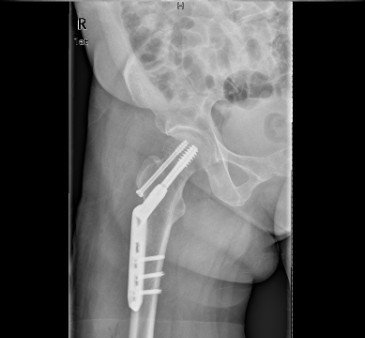

患者女,61岁,因“摔伤致右髋关节疼痛、活动受限9小时”入院。患者于入院前9小时行走时不慎摔倒,右侧肢体着地,当即感右髋关节及右大腿上段疼痛,活动受限,不能自行站立,受伤时及伤后无昏迷,无恶心、呕吐,无心累、气促,无腰痛及肉眼血尿。因休息后无缓解,急诊到当地医院行骨盆平片提示“右股骨颈骨折”,未做任何治疗,患者为求进一步治疗,遂急诊来我院,急诊以“右股骨颈骨折”收入住院。

查体:右髋关节、右大腿皮肤完整性好,右下肢轻度外旋。右腹股沟中点压痛明显,右股骨无明显压痛,未扪及明显骨擦感。右髋关节主被动活动受限。右下肢较左下肢短缩1cm。 辅查:院外X片右股骨颈骨折。

诊断:1、右股骨颈骨折(Garden III);2、骨质疏松症 治疗:择期手术